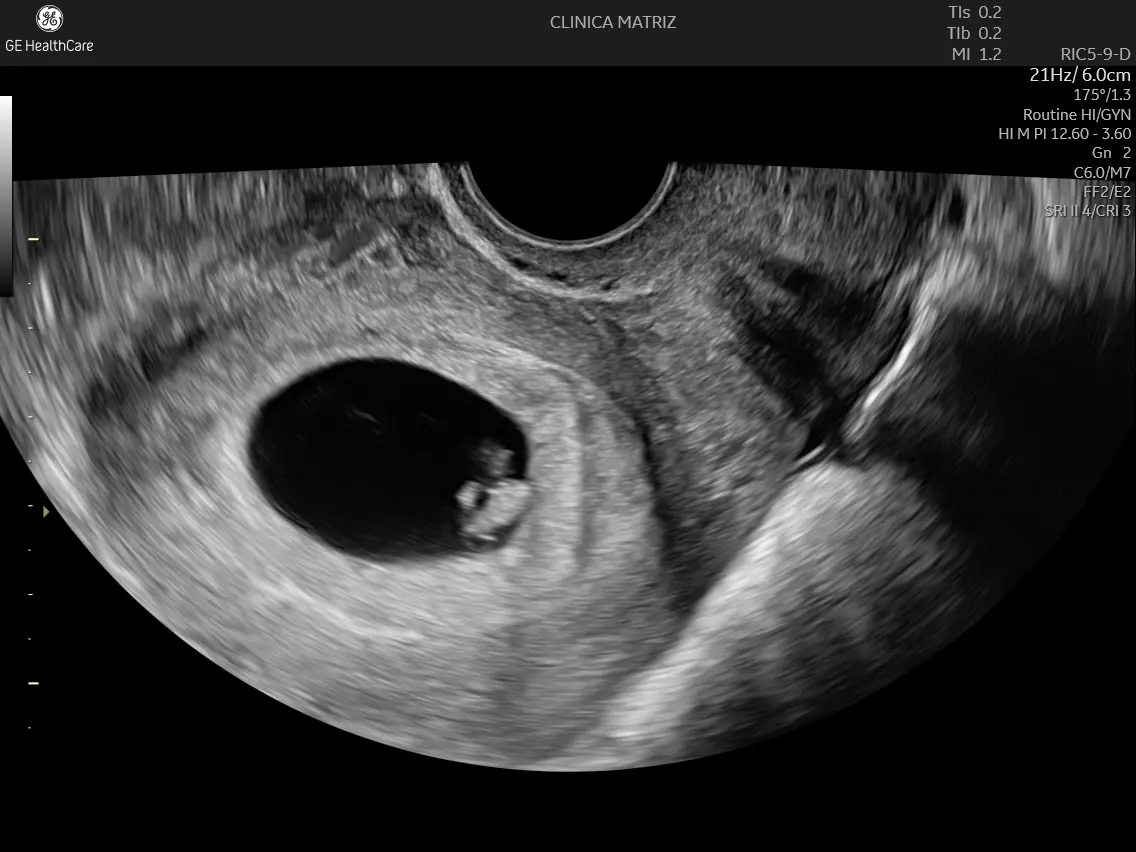

- Transvaginal, mais frequente no início da gravidez (quando é preciso ver estruturas muito pequenas com maior detalhe);

6–10 semanas: ecografia obstétrica precoce (avaliação inicial)

Pode ajudar a:

- confirmar se a gravidez é intrauterina;

- avaliar viabilidade (por exemplo, batimento cardíaco, quando já é expectável);

- estimar a idade gestacional e apoiar a definição da data provável do parto;

- identificar gestação única ou múltipla.

É também uma ecografia frequentemente pedida quando há dor, hemorragia, ou quando a datação é incerta.